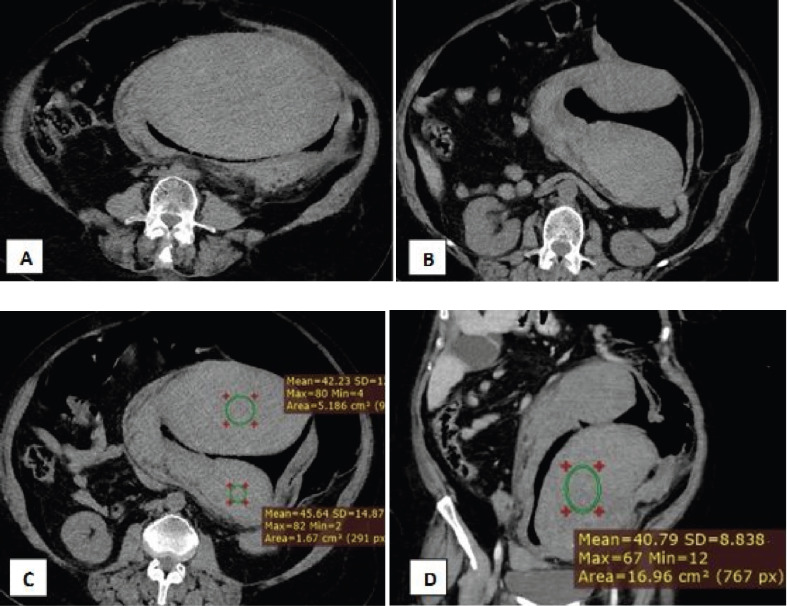

Patients on anticoagulation therapy, particularly those on warfarin, are at risk of gastrointestinal bleeding, gum bleeding, hematuria, and ecchymosis. However, it is rare for such patients to present with intramural or submucosal bleeding leading to intestinal obstructive symptoms. Sub-mucosal intestinal bleeding due to prolonged anticoagulant use is uncommon. Literature suggests that the duodenum and small intestine are common locations for anticoagulant-induced hematomas, occurring in approximately 1 case per 2,500 anticoagulated patients per year. However, intramural colonic hematomas are rarely reported. Spontaneous anticoagulant induced hematomas may develop as early as 10 days after starting therapy. We report the case of a 63-year-old female who presented with recto-sigmoid sub-mucosal bleeding causing obstructive symptoms. The patient was managed surgically with laparotomy, resulting in significant improvement, and was scheduled for follow-up to evaluate the feasibility of reintroducing anticoagulation therapy.